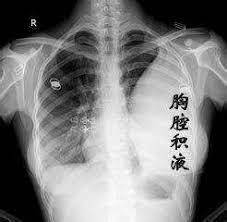

今年10月20日,老人身体状况急转直下。护理医生去他家照顾他时,发现他的胸部感染异常严重,胸部充满积液。

示意图,胸腔积液会导致人类胸疼、呼吸困难

而且,他的血氧含量已经严重不足,只有70%-80%!

一般的正常人,这个数值应该在94%以上......